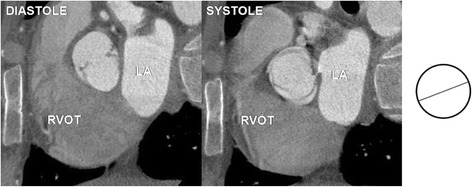

Fig. 2.

Unicuspid aortic valve - single lunar shape leaflet and single commissure. Note small orifice area responsible for stenotic dysfunction of the valve. RVOT – right ventricular outflow tract, LA – left atrium